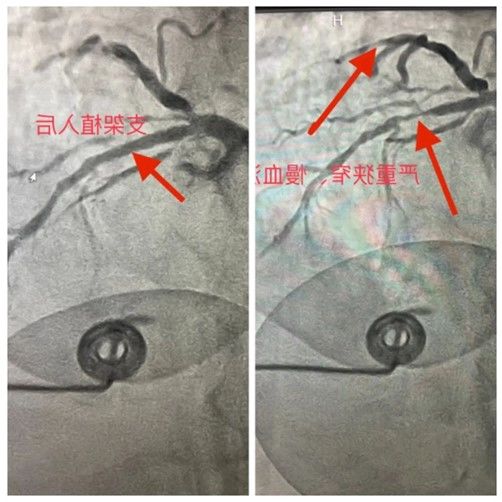

患者被紧急推进了手术室,情况十分危急。由于肺功能差,他的血氧饱和度仅为83%,远低于正常水平。冠状动脉造影显示,患者的心脏血管严重闭塞,前降支95%-99%闭塞,回旋支90%闭塞。这就是导致患者心肌缺血的罪魁祸首!

心血管病院二科的高宇勤主任团队深知时间的紧迫,他们凭借精湛的技艺和丰富的经验,精准、快速地为患者开通了急性闭塞血管,并成功植入支架一枚。